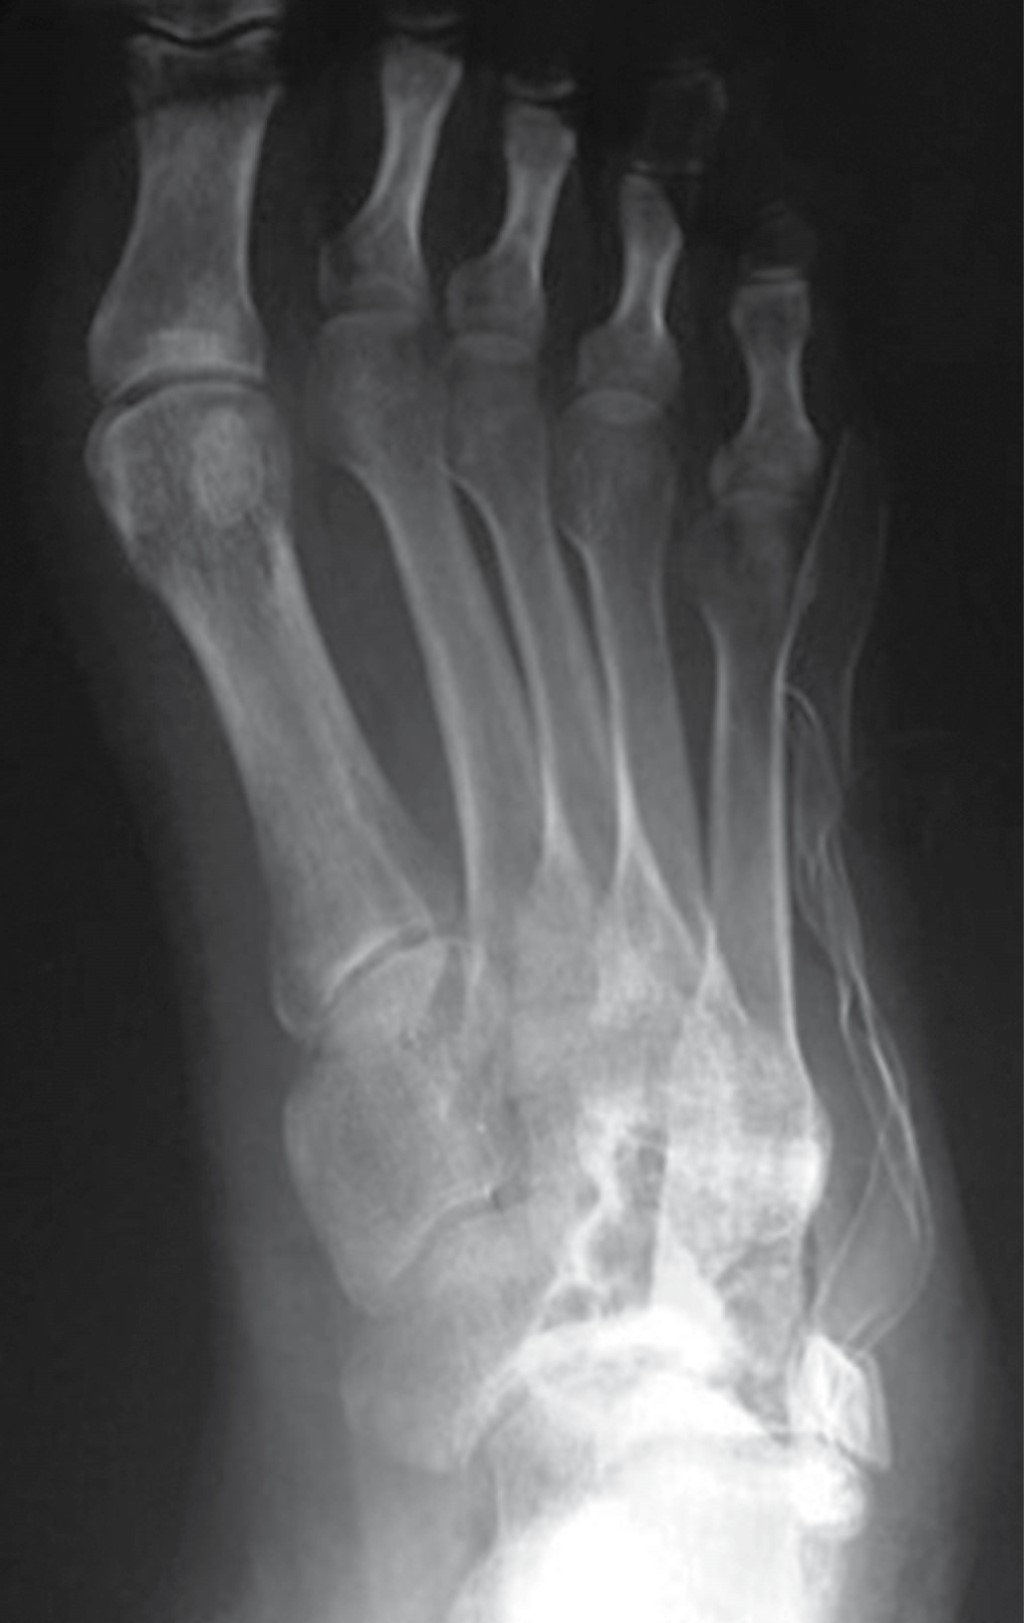

En las radiografías dorsoplantar y lateral de pie derecho se observa injerto óseo en el centro de una lesión en cuboides, radiotransparente, heterogénea, multilobulada, con bordes irregulares que sobrepasan la cortical lateral, multilobulados (Figuras 2 y 3).

Como estudios complementarios se encontró en la angiotomografía evidencia de la lesión hipervascularizada en casi todo el cuboides; en la gammagrafía con Tecnecio 99 se observa una captación del radiomarcador y la resonancia magnética reportó cambios postquirúrgicos en cuboides y una lesión ósea de aspecto quístico multilobulado.